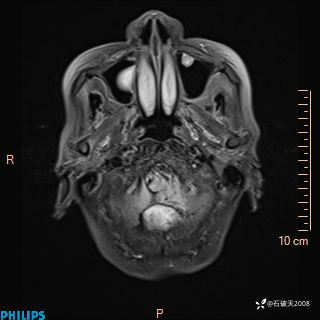

女 86岁 主 诉:乏力1月

现病史:患者1月前活动出现双下肢乏力,无头晕、头痛、恶心、呕吐、肢体活动不利,休息后缓解,间断断发作,症状进行性加重,在家口服药物治疗(具体不详),效差,为进一步诊治,来我院,门诊按“乏力”收住我科,患者自发病以来,神志清,精神稍差,饮食睡眠欠佳,大小便正常,体重未见明显改变。

ADC

增强轴位